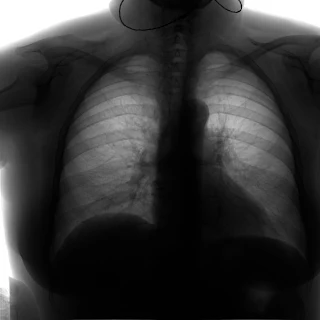

Флюорограма №46

Легені без вогнищево - інфільтративних змін. Корені не змінені. Синуси вільні. Серце норма. Сколіоз вправо.